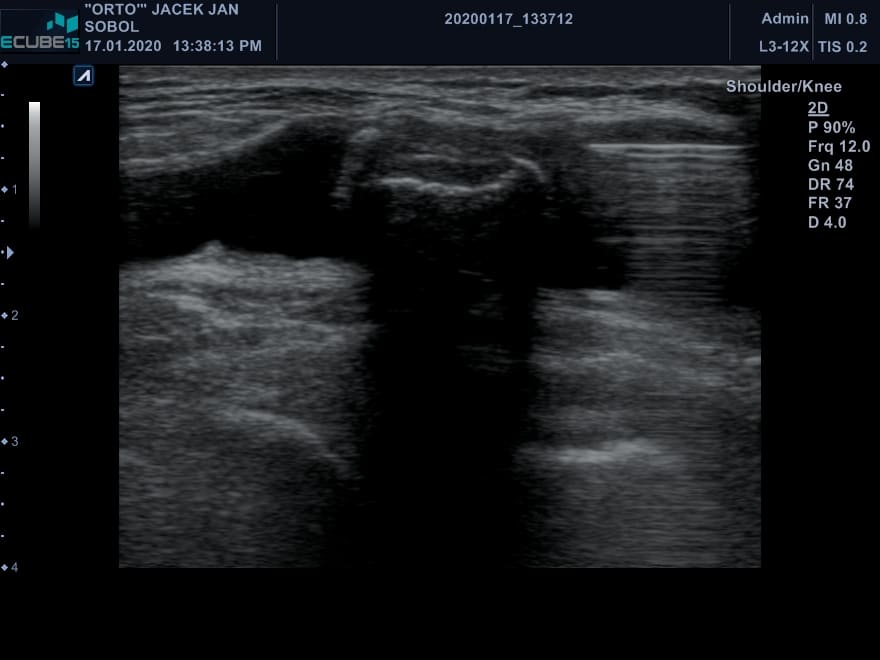

Przypadek pacjenta z dużą torbielą dołu podkolanowego. W obrębie torbieli widoczne duże cieniujące ciało wolne. Na ilustracji nr. 2 dodatkowo widoczna igła – punkcja torbieli, sprawdzenie mobilności ciała wolnego. Widoczny również tylny obrys kości udowej i piszczelowej. Torbiel dołu podkolanowego dobrze wypełniona, na długości całego obszaru obrazowania. Ciało wolne pochodzi najprawdopodobniej z jamy stawu kolanowego. Przypuszczalnie jest to fragment chrzęstno-kostny. Można je usunąć operacyjnie w trakcie artroskopii kolana.